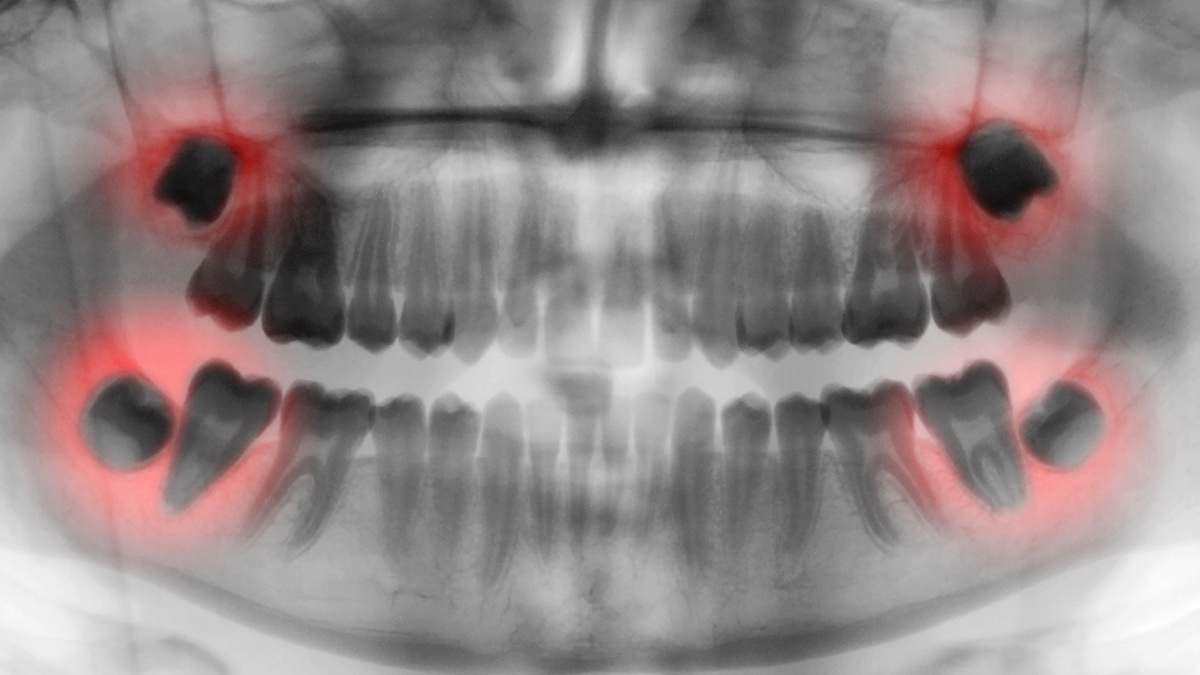

Diese Positionen werden in der Regel durch Panoramaröntgen oder eine zahnärztliche Tomographie (3D-Bildgebung) eindeutig bestimmt. Entsprechend werden die Behandlungsentscheidungen getroffen. In den Jimer Dental Clinics verwenden wir unsere modernen Panoramaröntgen- und Dentaltomographiegeräte (3D-Bildgebung), um eine detaillierte Visualisierung der Weisheitszähne im Knochen und ihrer Nähe zu den Nachbarzähnen zu ermöglichen und so eine wirksame Diagnose und Behandlung zu ermöglichen.

Drücken diese retinierten Zähne auf Nachbarzähne und liegen in der Nähe des Kiefernervs, müssen sie von einem Kieferchirurgen operativ entfernt werden, um Probleme zu vermeiden. Während der Weisheitszahnentfernung in den Jimer Dental Clinics erfolgt eine detaillierte Untersuchung und Diagnose mithilfe modernster Bildgebungsverfahren wie der 3D-Volumentomographie (CBCT) und Panoramaröntgen. Anhand radiologischer Bilder beurteilt der Kieferchirurg die Position des Zahns im Kieferknochen, seine Nähe zu den Nerven und Nachbarzähnen millimetergenau und erstellt anschließend den Operationsplan. Die Operationsplanung, insbesondere bei teilweise oder vollständig retinierten Weisheitszähnen, wird dank dieser fortschrittlichen Bildgebung deutlich sicherer.

Zuerst werden die Lage des Zahns, sein Abstand zum umliegenden Gewebe und seine Beziehung zu den Nerven gründlich untersucht. Es wird eine Panorama-Röntgenaufnahme oder, falls erforderlich, eine zahnärztliche Computertomographie (CT) angefertigt. Der Kieferchirurg wertet anschließend alle Bilder aus und erstellt einen Plan, der entscheidet, ob der Zahn durch einfache Extraktion oder chirurgische Entfernung entfernt wird.